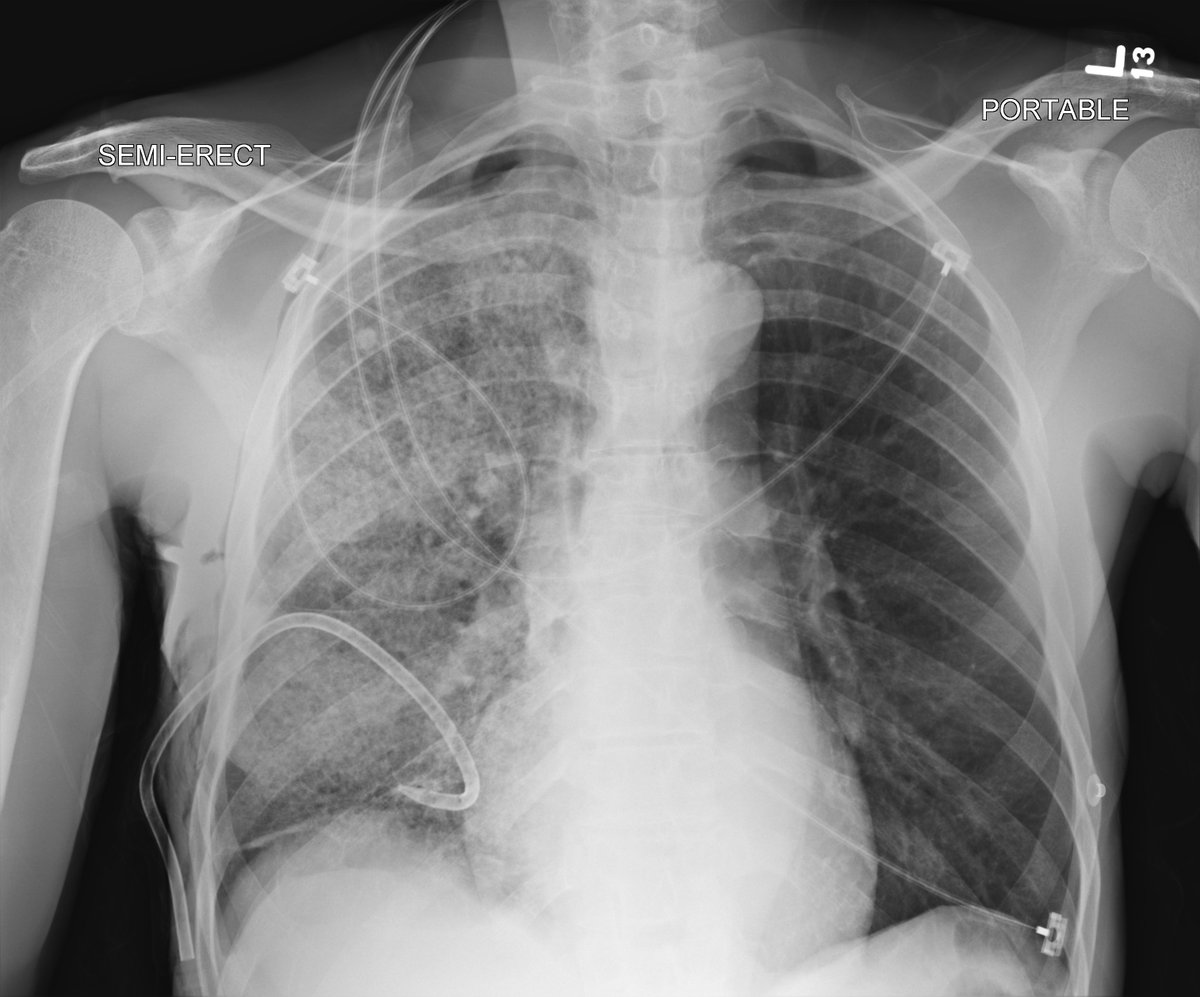

Re-expansion pulm. edema: rare important cause unilateral edema after (wait for it) rapid lung expansion after thoracentesis or PTX. Mortality up to 20%, prevent by removing < 1.5 L fluid. Complete recovery after < 1 week in this case. #chestraded #FOAMrad #FOAMed